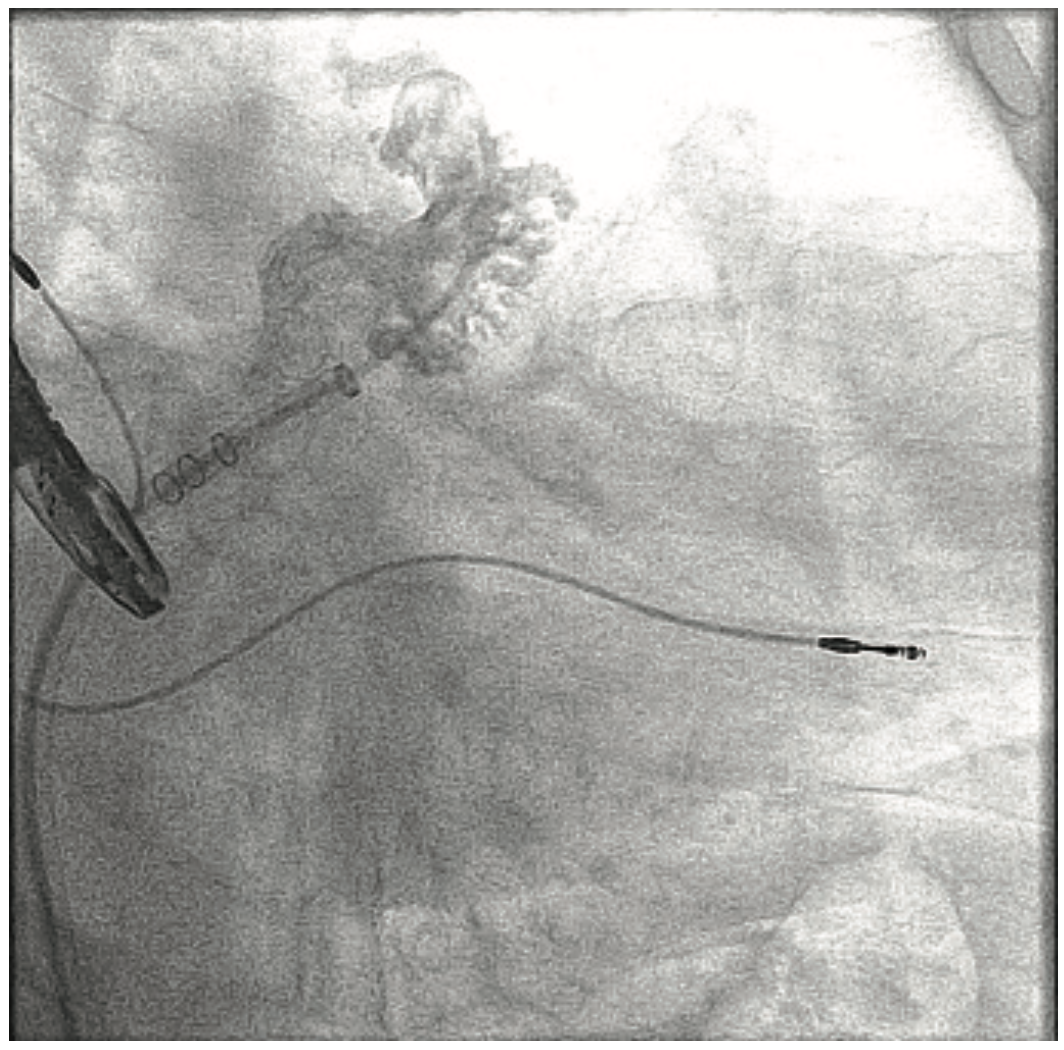

Source: sofmedica.com ACIST CVi Contrast Delivery System , 901479-002,01 2019-08 ACIST | CVi Contrast Delivery System User's Guide | 7 1 Introduction The ACIST| CVi® Contrast Delivery System is intended to be used for the controlled infusion of radiopaque contrast media for angiographic procedures • In order to avoid the potential for electric shock to the patient, do not

Source: www.youtube.com ACIST CVi Setting up YouTube , ACIST CVi is the contrast injector for: Interventional cardiologists who want to regulate contrast injection flow and minimize risk of CI-AKI—also referred to as contrast induced nephropathy (CIN); Hospital administrators interested in cost containment through cath lab safety and efficiency and reducing potential patient post-procedure adverse events • In order to avoid the potential for electric shock to the patient,.

Source: www.biosud.com.ar BioSud Argentina , The ACIST CVi system is designed and built to streamline procedures and deliver faster case turnaround, while minimizing the use of contrast The ACIST | CVi™ Contrast Delivery System (CVi system) is not intended for use as a long-term infusion pump